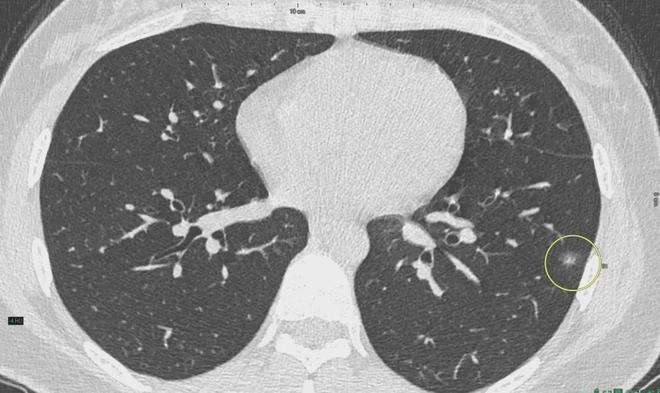

肺結節(jié)是一種常見的肺部疾病,其發(fā)病率逐年上升,雖然肺結節(jié)多數(shù)情況下是良性的,但也有可能惡化為肺癌,了解肺結節(jié)的形成原因對于預防和治療具有重要意義,本文將為您詳細解析肺結節(jié)的形成機制。

肺結節(jié)的形成原因

6、定期體檢:定期進行肺部檢查,及時發(fā)現(xiàn)并治療肺結節(jié)。

肺結節(jié)的形成是一個復雜的過程,涉及環(huán)境因素、遺傳因素、生活習慣和免疫系統(tǒng)等多個方面,了解這些成因有助于我們采取有效的預防措施,降低肺結節(jié)的發(fā)病風險,通過改善環(huán)境、戒煙限酒、健康飲食、規(guī)律作息、鍛煉身體和定期體檢等措施,我們可以更好地保護肺部健康,預防肺結節(jié)的發(fā)生。

對于已經發(fā)現(xiàn)肺結節(jié)的患者,應及時就醫(yī),進行進一步的檢查和治療,醫(yī)生會根據(jù)患者的具體情況制定個性化的治療方案,包括藥物治療、手術治療等,早期發(fā)現(xiàn)、早期治療是提高肺結節(jié)治愈率的關鍵。